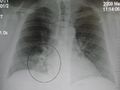

وعن طريق السماعة الطبية، يستطيع الطبيب أن يسمع أصواتًا مميزة آتية من الرئة تدل على وجود المرض. ويمكن لأشعة إكس (الأشعة السينية)، والاختبارات المعملية، أن تؤكد صحة التشخيص. أما تحديد نوع الميكروب المسبب للمرض، فإنه يتم عن طريق الاختبارات المعملية، إذ يقوم العامل الفني المتخصص بفحص عينة من بلغم المريض تحت المجهر. كما يعالج البلغم أيضًا بطرق مختلفة، حتى يمكن تنمية الكائن العضوي المُسبِّب للعدوى داخل المعمل، بحيث يمكن التعرف عليه.